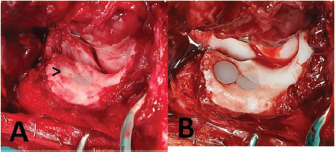

Fig. 8. Revision surgery in a case with septic arthritis and implant loosening 8 weeks after removal of the cranial ulnar implant. (A) Groove-like chondral and subchondral defect with signs of wear of the remaining implant, arrow—fibrocartilage infill of the former implant bed and (B) Over reamed bed of the initial implant with an implanted large-sized ulnar implant.

In all five cases with persistent lameness and pain, a second look arthroscopy was carried out. In two cases, an extension of a full-thickness chondral defect caudal to the ulnar implant was apparent and treated by implantation of one (n=1) or two (n=2) additional UImpl just caudal to the initial implant along the ulnar trochlea, using the modified caudo-medial approach and standard CUE implantation technique (Fig. 7). Further healing was uneventful, and at the last follow-up examination 2 and 10 months after revision surgery, both cases achieved an acceptable outcome with a LOAD score of 18.

Fig. 7. Case with persistent lameness and pain 6 months after CUE procedure. (A) Second-look arthroscopy showing an extension of full-thickness chondral defect caudal to the ulnar implant and (B) Medio-lateral radiographic view after revision surgery and implantation of two additional medium-sized ulnar implants.